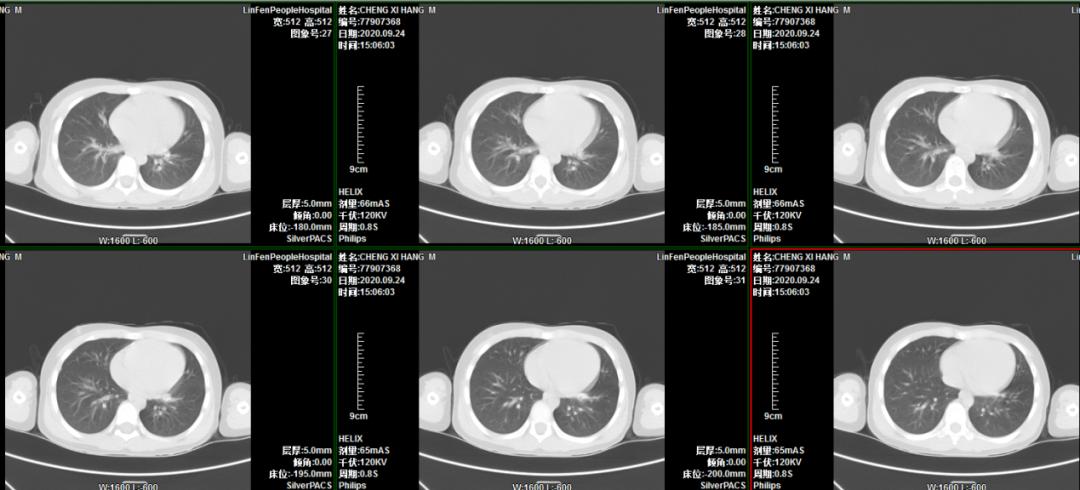

患儿程某,男,6岁3月,主因“间断咳嗽、喘息20天”入住我院普通儿科。入院后行胸部CT示左肺下叶不张,进一步增强扫描考虑左肺下叶支气管存在异物堵塞。考虑病程长,异物位于左肺下叶亚支,难度大。小儿呼吸科李荟主任积极邀请首都医科大学附属北京儿童医院呼吸儿科室杨海明主任、气管镜室李干主任亲临我院会诊指导,顺利进行了支气管镜检查及异物取出术,术后5天复查胸部CT肺不张完全恢复。

术前胸部CT